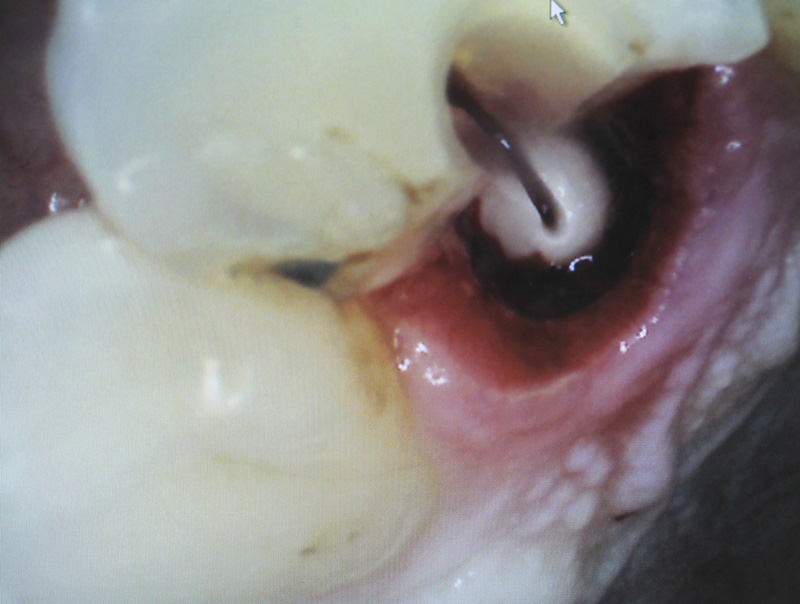

La paziente si presenta alla nostra osservazione con una frattura verticale di un primo premolare superiore.

Nella seduta d'uregenza sotto anestesia viene estratto il pezzo di radice fratturato ed eseguita un pulpectomia totale della polpa.

A distanza di qualche giorno viene esguita l'estrazione con l'aiuto di del Soniflex (Komet) con le rispettive punte al fine di non danneggiare l'osso corticale.